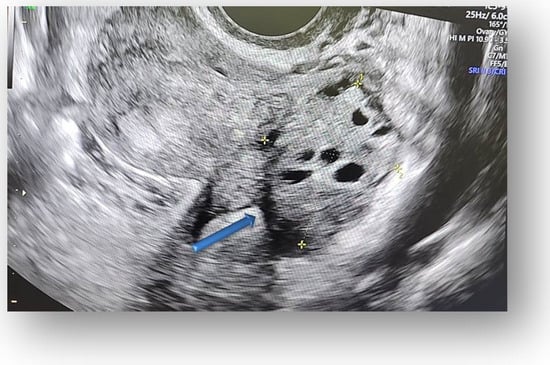

Figure 4.

The contralateral ovary has a normal appearance and size.